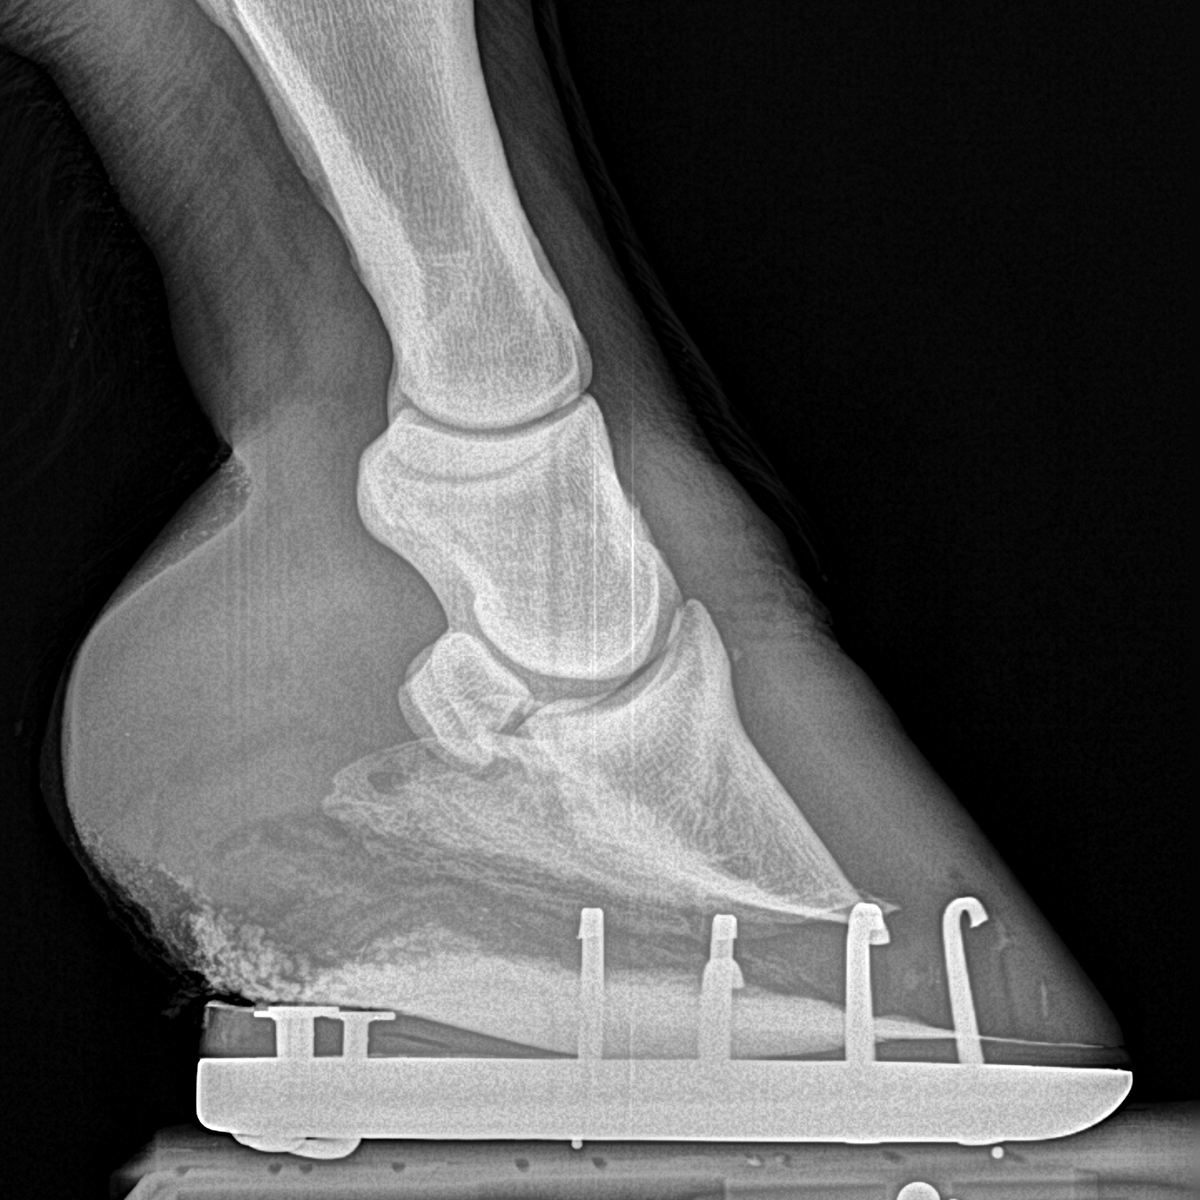

Michael Porter, Equine Veterinarian Extensor Process Fracture in a Horse Horse Side Bone Treatment In general, horses require at least three months of stall rest when treating sidebone fractures. Treatment for sidebone in horses to treat sidebone in horses, it’s important to first diagnose whether any lameness the horse has is from sidebone or from another cause. Treatment and management of sidebone in horses. Many horses compete actively in demanding. If sidebone is deemed. Horse Side Bone Treatment.

Michael Porter, Equine Veterinarian Extensor Process Fracture in a Horse Horse Side Bone Treatment Sidebone usually occurs in the forelimb,. This process can take months and during this time anti. There is no need to treat subclinical ossification of collateral cartilages. Rest is the key when it comes to treatment as it provides time for the inflammation to be reduced. If sidebone is deemed to be the cause of. In some cases the only. Horse Side Bone Treatment.